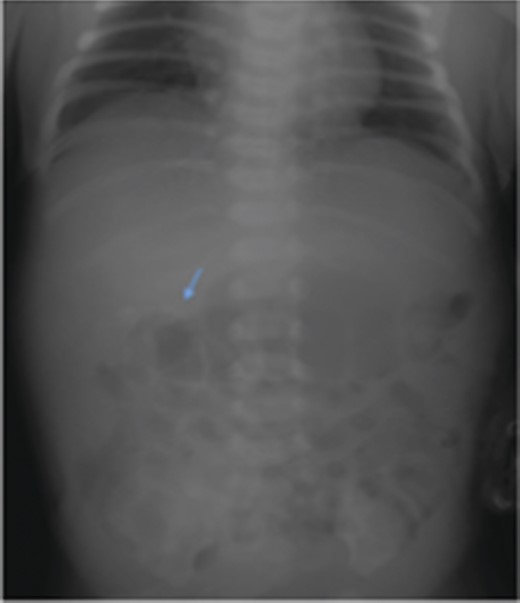

The case was referred to the Pediatric Surgery team postnatally. Birthweight was 3.6 kg. Apart from a distended abdomen, the child appeared grossly normal. Abdominal radiograph showed curvilinear calcifications over the right abdomen (Fig. 1). Ultrasonography (USG) revealed the presence of an echogenic line resembling long bones, giving rise to a provisional diagnosis of FIF (Fig. 2). An alpha feto protein (αfp) level taken at birth was markedly elevated at 13 200 IU/ml. Normal range of αfp at our center is taken to be 0–5.8 IU/ml at birth.